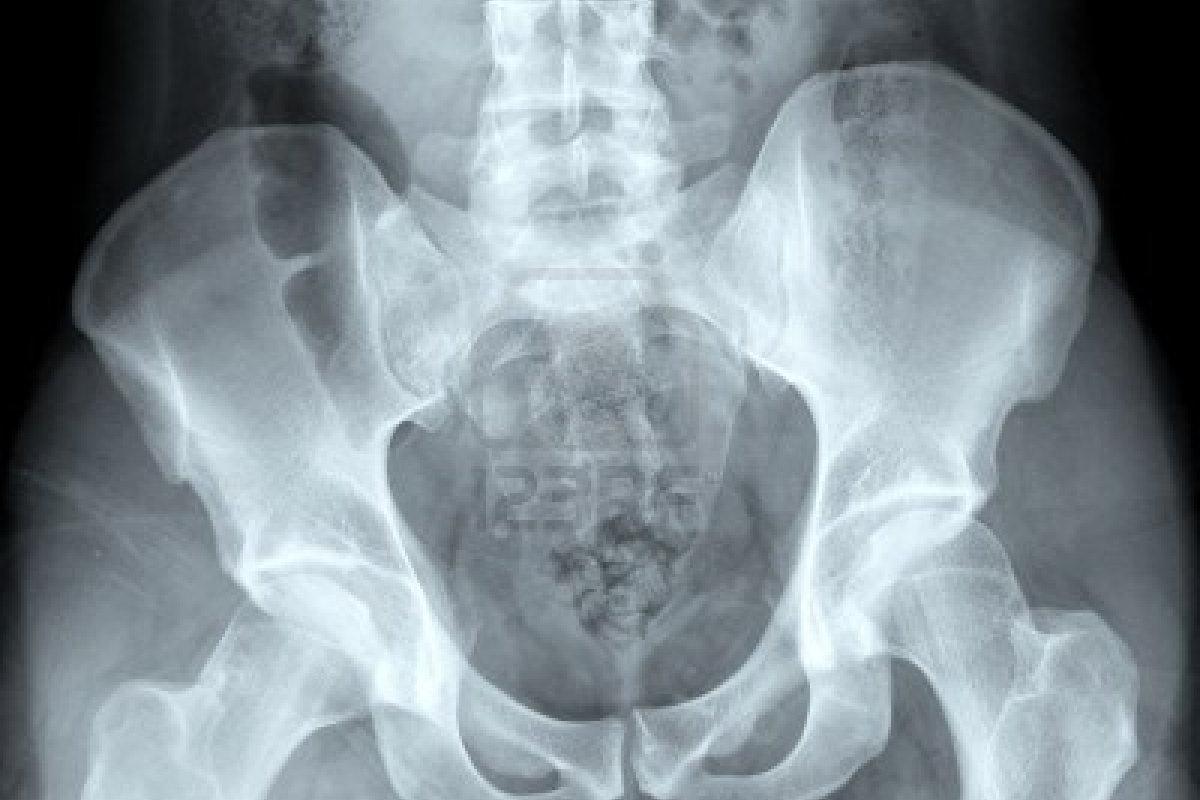

Por calhar no crescimento de esporões e alterar obrigatoriamente a ossatura da região danificada, a esclerose óssea pode ser detectada com radiografia, bastando uma análise médica para constatar o problema. Se o problema for, por exemplo, uma esclerose óssea no quadril, um simples exame de imagem da região será capaz de confirmar a suspeita.